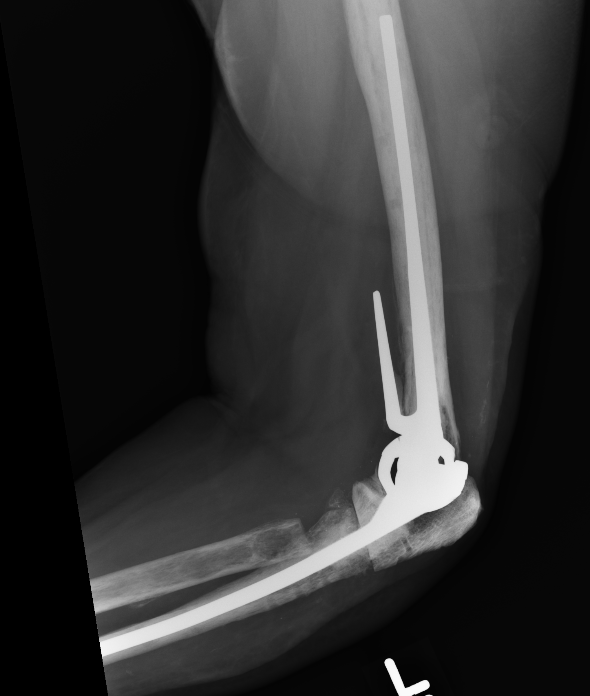

Coonrad-Morrey Discovery Elbow Latitude

Arthroplasty

4. Trial reduction

5. Insert cement restrictors / implant ulna and humeral prosthesis

6. Insert bone graft under anterior flange

7. Link components

8. Repair collaterals if needed